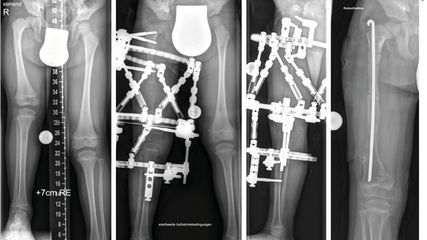

Abb. 3: Isometrische Dehnung der Kaumuskulatur: Zeige- und Mittelfinger auf die unteren Schneidezähne legen. Mund öffnen, ausatmen, Luft anhalten. Mit den Fingern Kiefer leicht nach unten drücken, dabei Kiefer mit wenig Kraft dagegendrücken. Einatmen, Luft anhalten, dabei Kiefer entspannen und Kiefer weiter nach unten ziehen

Abb. 4: Kiefer nach vorne bewegen gegen Widerstand: Zeige- und Mittelfinger an die Kinnspitze legen. Kinn nach vorne schieben, mit den Fingern dagegenhalten. Einatmen und Luft für 5 Sekunden anhalten. Gegendruck der Finger beibehalten. Ausatmen, entspannen. 5x wiederholen

Muskulatur isometrisch dehnen: Zeige- und Mittelfinger auf die unteren Schneidezähne legen (Abb. 3). Mund öffnen, ausatmen, Luft anhalten. Mit den Fingern Kiefer leicht nach unten drücken, dabei Kiefer mit wenig Kraft dagegendrücken. Einatmen, Luft anhalten, dabei Kiefer entspannen und Kiefer weiter nach unten ziehen.

Kiefer nach vorne bewegen gegen Widerstand: Zeige- und Mittelfinger an die Kinnspitze legen (Abb. 4). Kinn nach vorne schieben, mit den Fingern dagegenhalten. Einatmen und Luft für 5 Sekunden anhalten. Gegendruck der Finger beibehalten. Ausatmen, entspannen. 5x wiederholen.